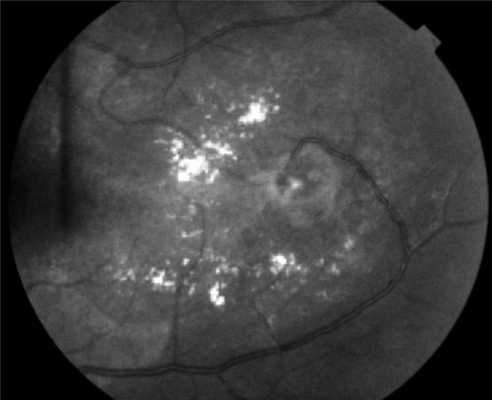

Поражения глаз выявляются примерно у 37% пациентов с VHL-синдромом, среди них только у 14% обнаруживается полная делеция VHL [51, 52]. Приблизительно у 8% пациентов снижена острота зрения [53]. Для лечения ангиомы сетчатки используют лазерную или криотерапию [32, 34, 54]. Недавние исследования [ 55, 56] показали, что при внутривенном введении антагониста сосудистого эндотелиального фактора роста (anti-VEGF) в течение 7 мес размер гемангиобластом не уменьшается (рис. 3). Рисунок 3. Ангиоматоз сетчатки.

Предполагать и исключать болезнь Гиппеля-Линдау следует в каждом случае выявления ангиоматоза сетчатки в ходе офтальмоскопии, особенно при наличии отягощенного семейного анамнеза. В начальной стадии офтальмоскопия может определять одиночную ангиому сетчатки с дилатацией питающих ее сосудов, впоследствии ангиомы становятся множественными, характерны аневризмы и змееобразная извитость сосудов. Диагностировать самые ранние изменения сосудов сетчатки и стертые формы позволяет флюоресцентная ангиография сетчатки. С ее помощью можно дифференцировать изменения сетчатки, сопровождающие болезнь Гиппеля-Линдау, от другой офтальмологической патологии: ретинопатий, ритинита, ретинобластомы, нейропатии зрительного нерва и пр. Уточнение диагноза возможно при помощи лазерной томографии сетчатки.